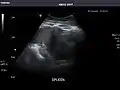

Spleen

Spleen: Normal in size.